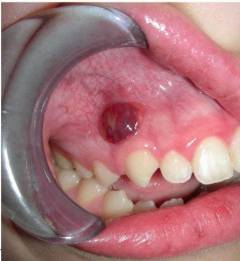

Хронический гипертрофический пульпит характеризуется разрастанием пульпы, образующей полип, что вызывает болезненность при жевании и кровоточивость.

| Гипертрофический пульпит | * Кровоточивость при жевании и чистке зубов; * Внутри глубокой полости можно увидеть розовую массу – разрастание пульпы. |

Хронический гипертрофический пульпит – форма заболевания, при которой кариозная полость соединяется с полостью зуба. Пульпа разрастается, образуя полип, который заполняет пространство. У пациента возникает болезненность при жевании и кровоточивость из зуба. Эти ощущения сменяются сильными болями, характерными для острого периода.

| Гипертрофический пульпит | * Кровоточивость при жевании; * Видимая розовая масса в полости. |

- Образование красного пузырька на десне, который может образовать свищ.